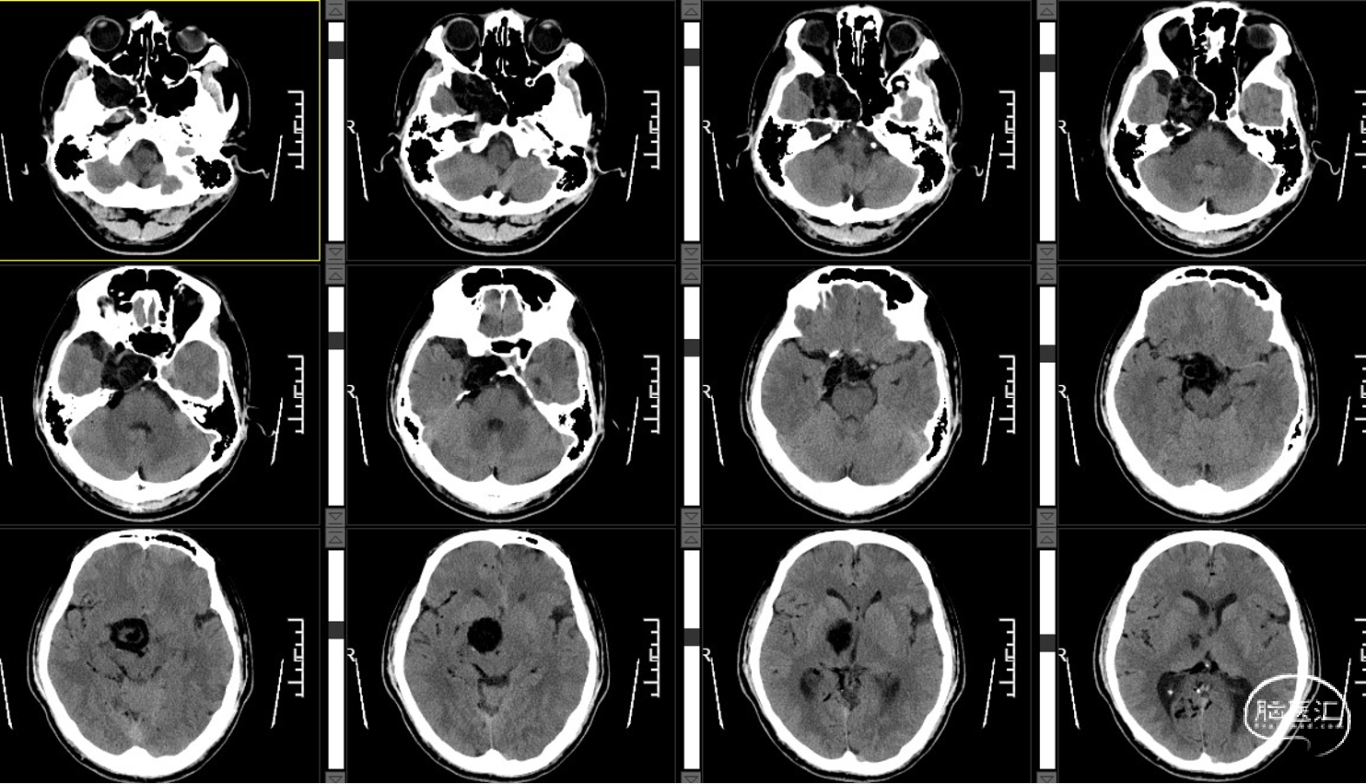

外院CT示:右侧颅底占位性病变,临近骨质部分吸收。